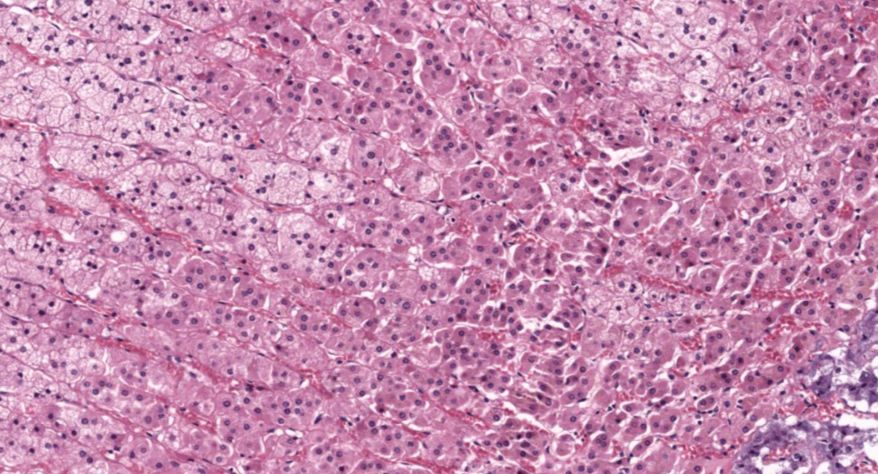

弥漫性非毒性甲状腺肿:甲状腺滤泡明显扩张,内含大量胶质,滤泡上皮细胞受压呈扁平状。部分上皮增生,可见小滤泡和小假乳头形成。

1.全景图

2.纤维组织包膜

3.滤泡上皮增生

4.滤泡扩张